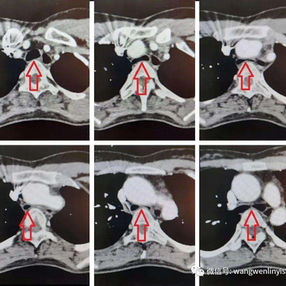

Preoperative Examination

The patient’s thoracic spine is unnaturally flat with a slight forward curvature at the upper thoracic vertebrae, reducing the distance between it and the anterior chest wall. Additionally, the ascending aorta is dilated, and the trachea is noticeably compressed, particularly severely at the start of the aortic arch. The patient was ultimately diagnosed with flatback syndrome combined with severe tracheal stenosis.